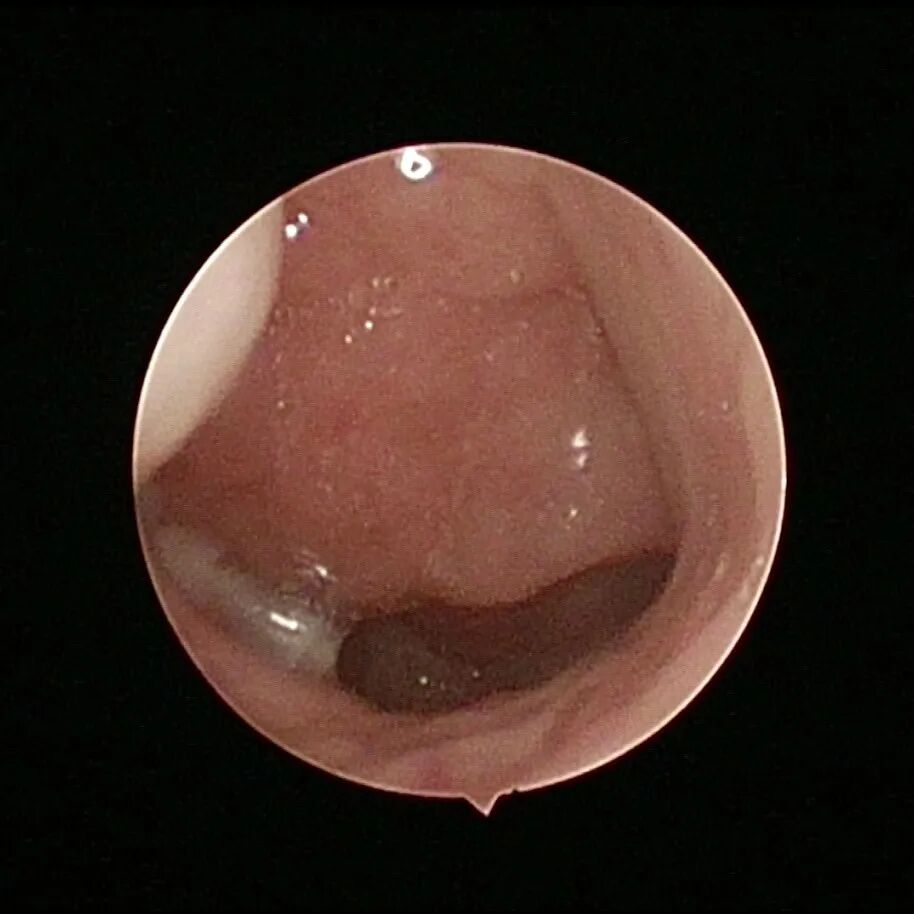

腺样体增生

1